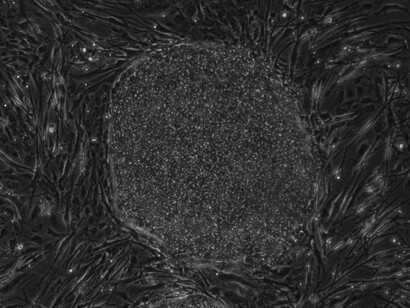

Mesenchymal stem cells (MSCs) are stromal cells that can differentiate into many lineages and self-renew. Numerous tissues, including the umbilical cord, endometrial polyps, menstrual blood, bone marrow, adipose tissue, etc., can yield MSCs.

Cells from bone marrow or adipose tissue are harvested, processed, and then reintroduced into the injured area. This strategy allows your body to repair naturally, resulting in less pain and a speedier recovery.